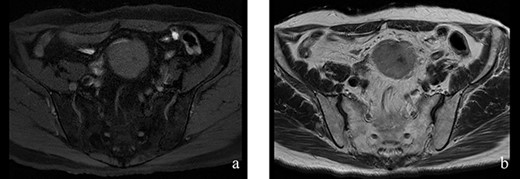

A 70-year-old man underwent robot-assisted laparoscopic cystectomy with bladder replacement for bladder cancer. The pathological diagnosis was stage 0 (Tis, N0, M0). Nine months after the operation, no plain computed tomography (CT) findings indicated cancer recurrence. Thirteen months after the operation, contrast-enhanced CT showed a well-defined intra-abdominal mass, up to 50 × 40 mm in size, with heterogeneous enhancement. The tumor was in contact with the small intestine (Fig. 1). Magnetic resonance imaging (MRI) revealed an isolated mass with hypointensity on T1-weighted images and mild hyperintensity on T2-weighted images (Fig. 2a and b). Fluorine-18 fluorodeoxyglucose positron emission tomography CT (FDG-PET/CT) revealed mild FDG uptake in the tumor, with a maximum standardized uptake value (SUV max) of 3.4 (Fig. 3). Based on these findings, bladder cancer recurrence or mesenchymal tumors derived from the small intestine or mesentery were suspected. The tumor showed a rapid growth trend and required immediate therapeutic intervention. However, a differential diagnosis based on the imaging findings alone was difficult to achieve. Therefore, we decided to perform a diagnostic surgery to identify the intra-abdominal tumor.

Figure 2: (a, b) The tumor had hypointensity on the T1-weighted images and mild hyperintensity on the T2-weighted images.

Desmoid tumors can be found accidentally during postoperative follow-up of any cancer, and in such cases, the differentiation of desmoid tumors and cancer recurrence is often necessary. There have been reported two cases that developed after cystectomy for bladder cancer [5, 6]. CT showed that the tumor was a well-circumscribed homogeneous lesion with isodence or hyperdensity relative to the muscle [7]. On MRI findings, it often demonstrates hypointensity on T1-weighted images and heterogeneity on T2-weighted images [7]. However, these imaging findings are not specific to desmoid tumors. Mesenteric desmoid tumors can accumulate FDG uptake on PET-CT [2, 8]. Furthermore, FDG-PET/CT has been shown to be useful in assessing the response to treatment, but its role in assessing desmoid tumors remains unclear [8]. The above information underscores the difficulty of diagnosing desmoid tumors from imaging findings alone. In our case, cancer recurrence in the small intestine or mesentery was also differentiated. A prior study reported that, of bladder cancers with distant metastasis, only 3% were found in the intestine [9]. Thus, the small intestine or mesentery is not a predilection metastatic site of bladder cancer, and when a tumor develops from the small intestine mesentery and is found following surgery for bladder cancer, it may be necessary to immediately perform a diagnostic surgery.